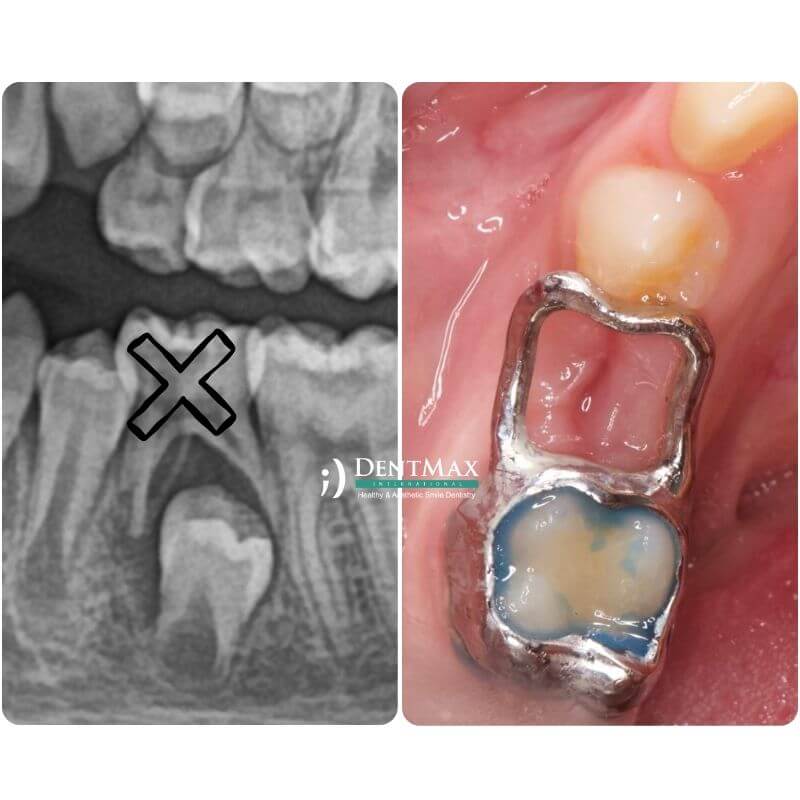

Çocuklarda Diş Çekimi